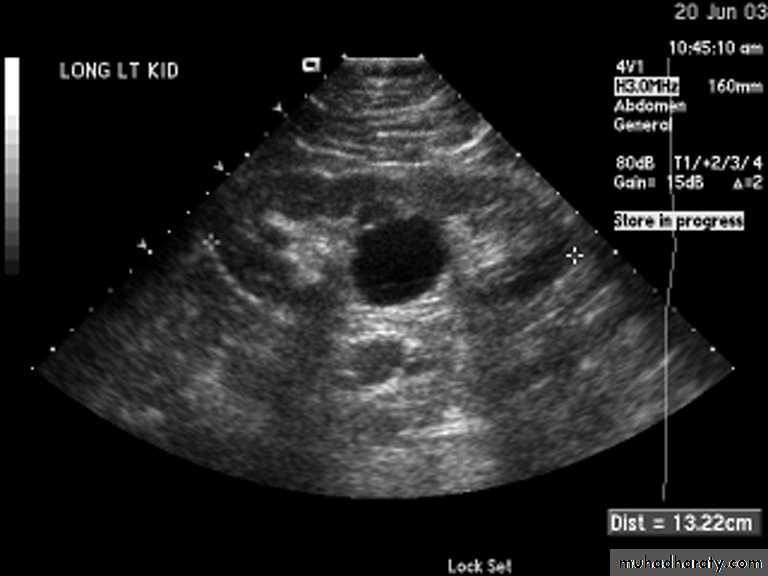

Simple (solitary) renal cyst

Common condition.

single or multiple.

uni or bilateral.

Congenital or acquired.

Usually asymptomatic.

In 10% symptomatic: pain, heaviness, infection, bleeding inside the cyst or

pressure effect on the ureter causing hydronephrosis.

Diagnosis

Examination: usually –ve, big cyst cause painless loin mass, & painful if complicated by bleeding or infection

U/S: echo free area (cystic lesion)

KUB: soft tissue shadow.

IVU: stretched calyx, filling defect or hydronephrosis.

CT scan &MRI: are diagnostic.